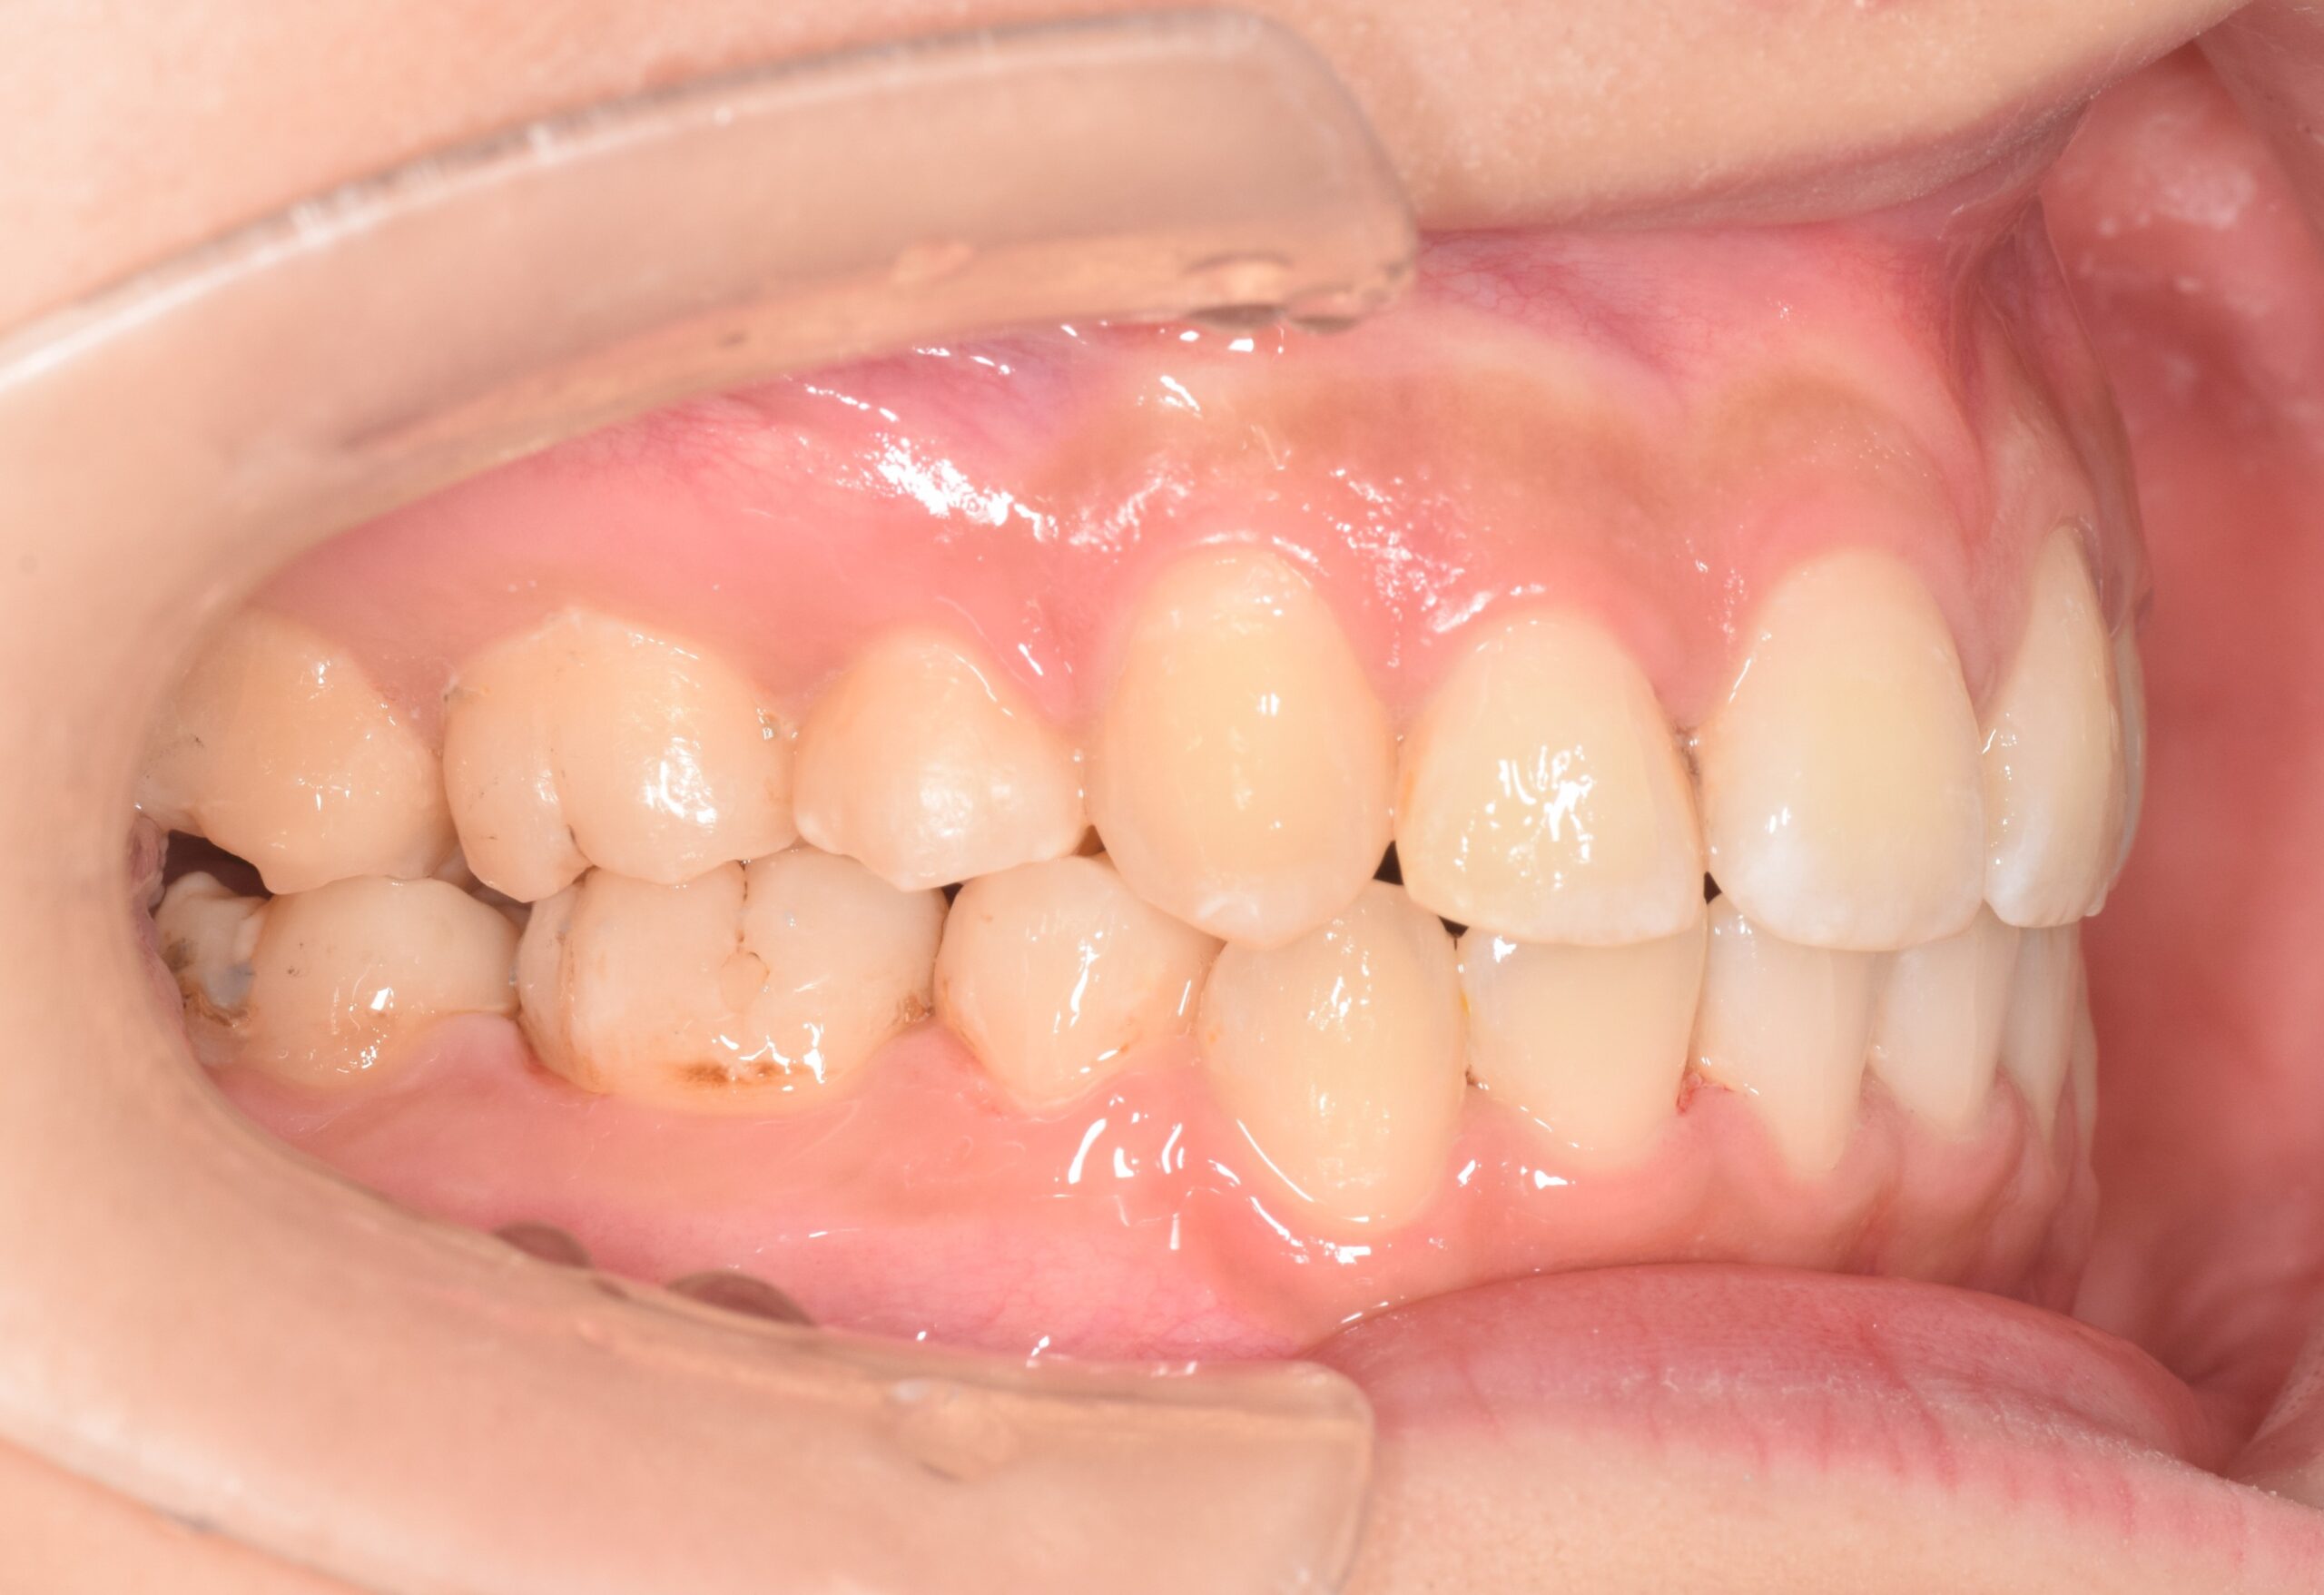

AFTER

| 年齢 | 19歳 |

|---|---|

| 主訴 | ガタガタが気になる |

| 症状 | 過蓋咬合を伴う叢生症例 |

| 治療内容 | 過蓋咬合を伴う叢生症例と診断し上下顎両側第一小臼歯の抜歯を行い、マルチブラケット装置を用いて治療を行いました。上顎は裏側の矯正装置、下顎は表側の矯正装置で治療を行いました。ハーフリンガル矯正治療。 |

| 抜歯部位 | 上下顎両側第一小臼歯 |

| 治療期間 | 3年 |

| 費用(税込) | 1,045,000(税込)別途処置料 |

| 治療のリスク | 虫歯、歯周病の悪化、歯肉退縮、歯根吸収、顎関節症の悪化、後戻り |